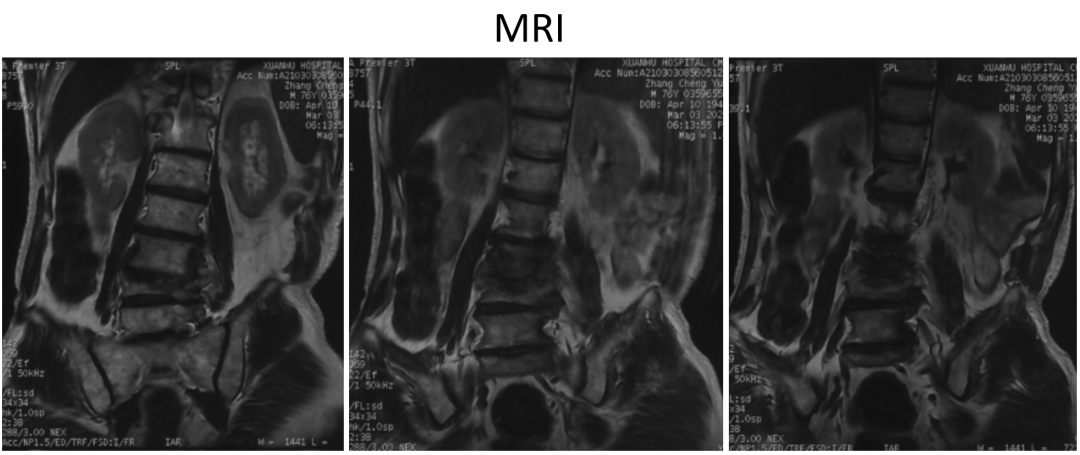

讨论主题:L4压缩骨折伴脊柱侧后凸畸形

影像资料:

腰椎侧后凸畸形

腰椎陈旧性压缩性骨折(L4)